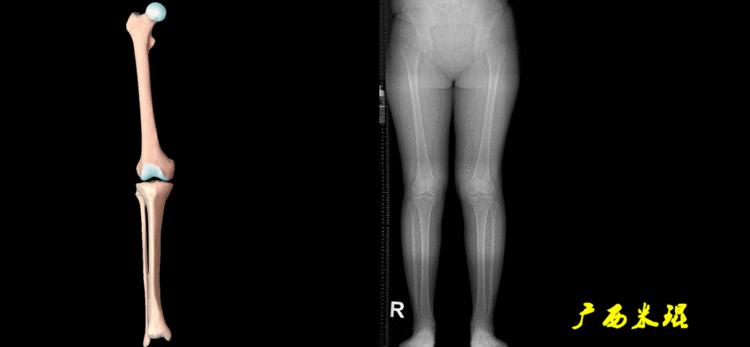

(2)机械轴

机械轴是连接近端和远端关节中心点的直线。

机械轴要分前后位及侧位,站立前后位(也就是冠状面)股骨头中心与踝关节中心的连线通过膝关节中心,这是下肢的机械轴线,也就是下肢力线,常说Mikulicz线。冠状面的力线评估在临床工作中最常用、最基础、最重要。

站立侧位(矢状面)股骨头中心与踝关节中心的连线也通过膝关节中心,这也是下肢的机械轴线,这也是下肢力线。

矢状面的下肢力线常常被医生忽视,其实它的改变也是膝关节疼痛的常见原因。

我们说了这么多照片的下肢力线测量,体表也是可以粗略测量的,自股骨头中心至踝关节中心拉一直线,髌骨中心点位于此直线上;自髂前上棘至踝关节中心拉一直线,髌骨中心点位于此直线内侧;自髂前上棘至第1、2趾间拉一直线,髌骨中心点位于或接近此直线。

(3)垂直轴

也就是下肢的负重轴,它是身体的纵轴线,与地面垂直,由于双髋比双踝的距离宽,所以垂直轴与下肢力线(机械轴)存在3°的外翻。

开始接触时可能我们对这些轴有点混乱,通过下面的这张图片就能清楚的了解下肢几个轴之间的关系。